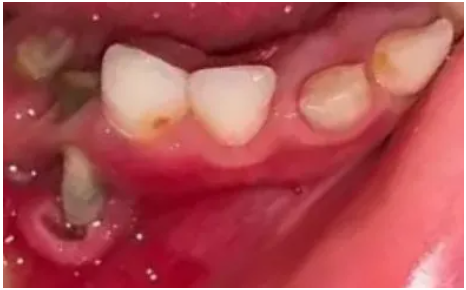

1.引起疼痛

乳牙蛀牙锐利边缘,损伤到孩子的口腔黏膜造成口腔溃疡,或发展成牙髓炎,引起剧烈疼痛。

龋齿造成口腔溃疡